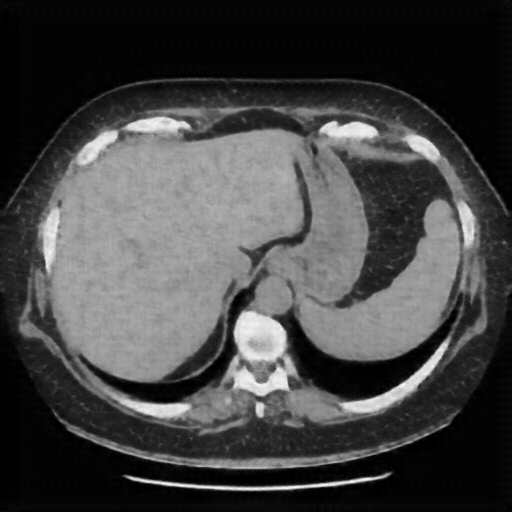

Generated VENOUS CT scan (A→B translation)

Full window (WL 1023.5, WW 4095 β†’ Low βˆ’1024, High +3071)

Lung window (WL -600, WW 1500 β†’ Low βˆ’1350, High +150)